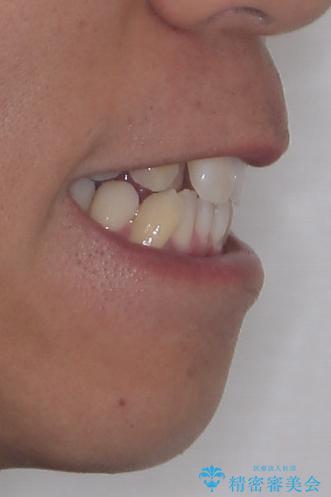

上下の前歯部に強い叢生(ガタガタの歯並び)があり、そのまま歯を並べると出っ歯になってしまう可能性がありました。

八重歯はきれいに整い、前歯もバランスよく収まり、横顔のラインも自然に改善されました。

治療後、患者様は「思い切り笑えるようになった」と大変喜んでくださいました。